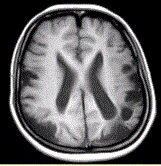

问题 女性,22岁。癫痫发作及智力异常。MRI显示见下图。 关于该病,最可能的原因是

选项 A.海绵状血管瘤 B.发育性静脉畸形 C.AVM D.毛细血管扩张症 E.动脉瘤 F.硬脑膜动静脉瘘 G.moyamoya

答案 CG